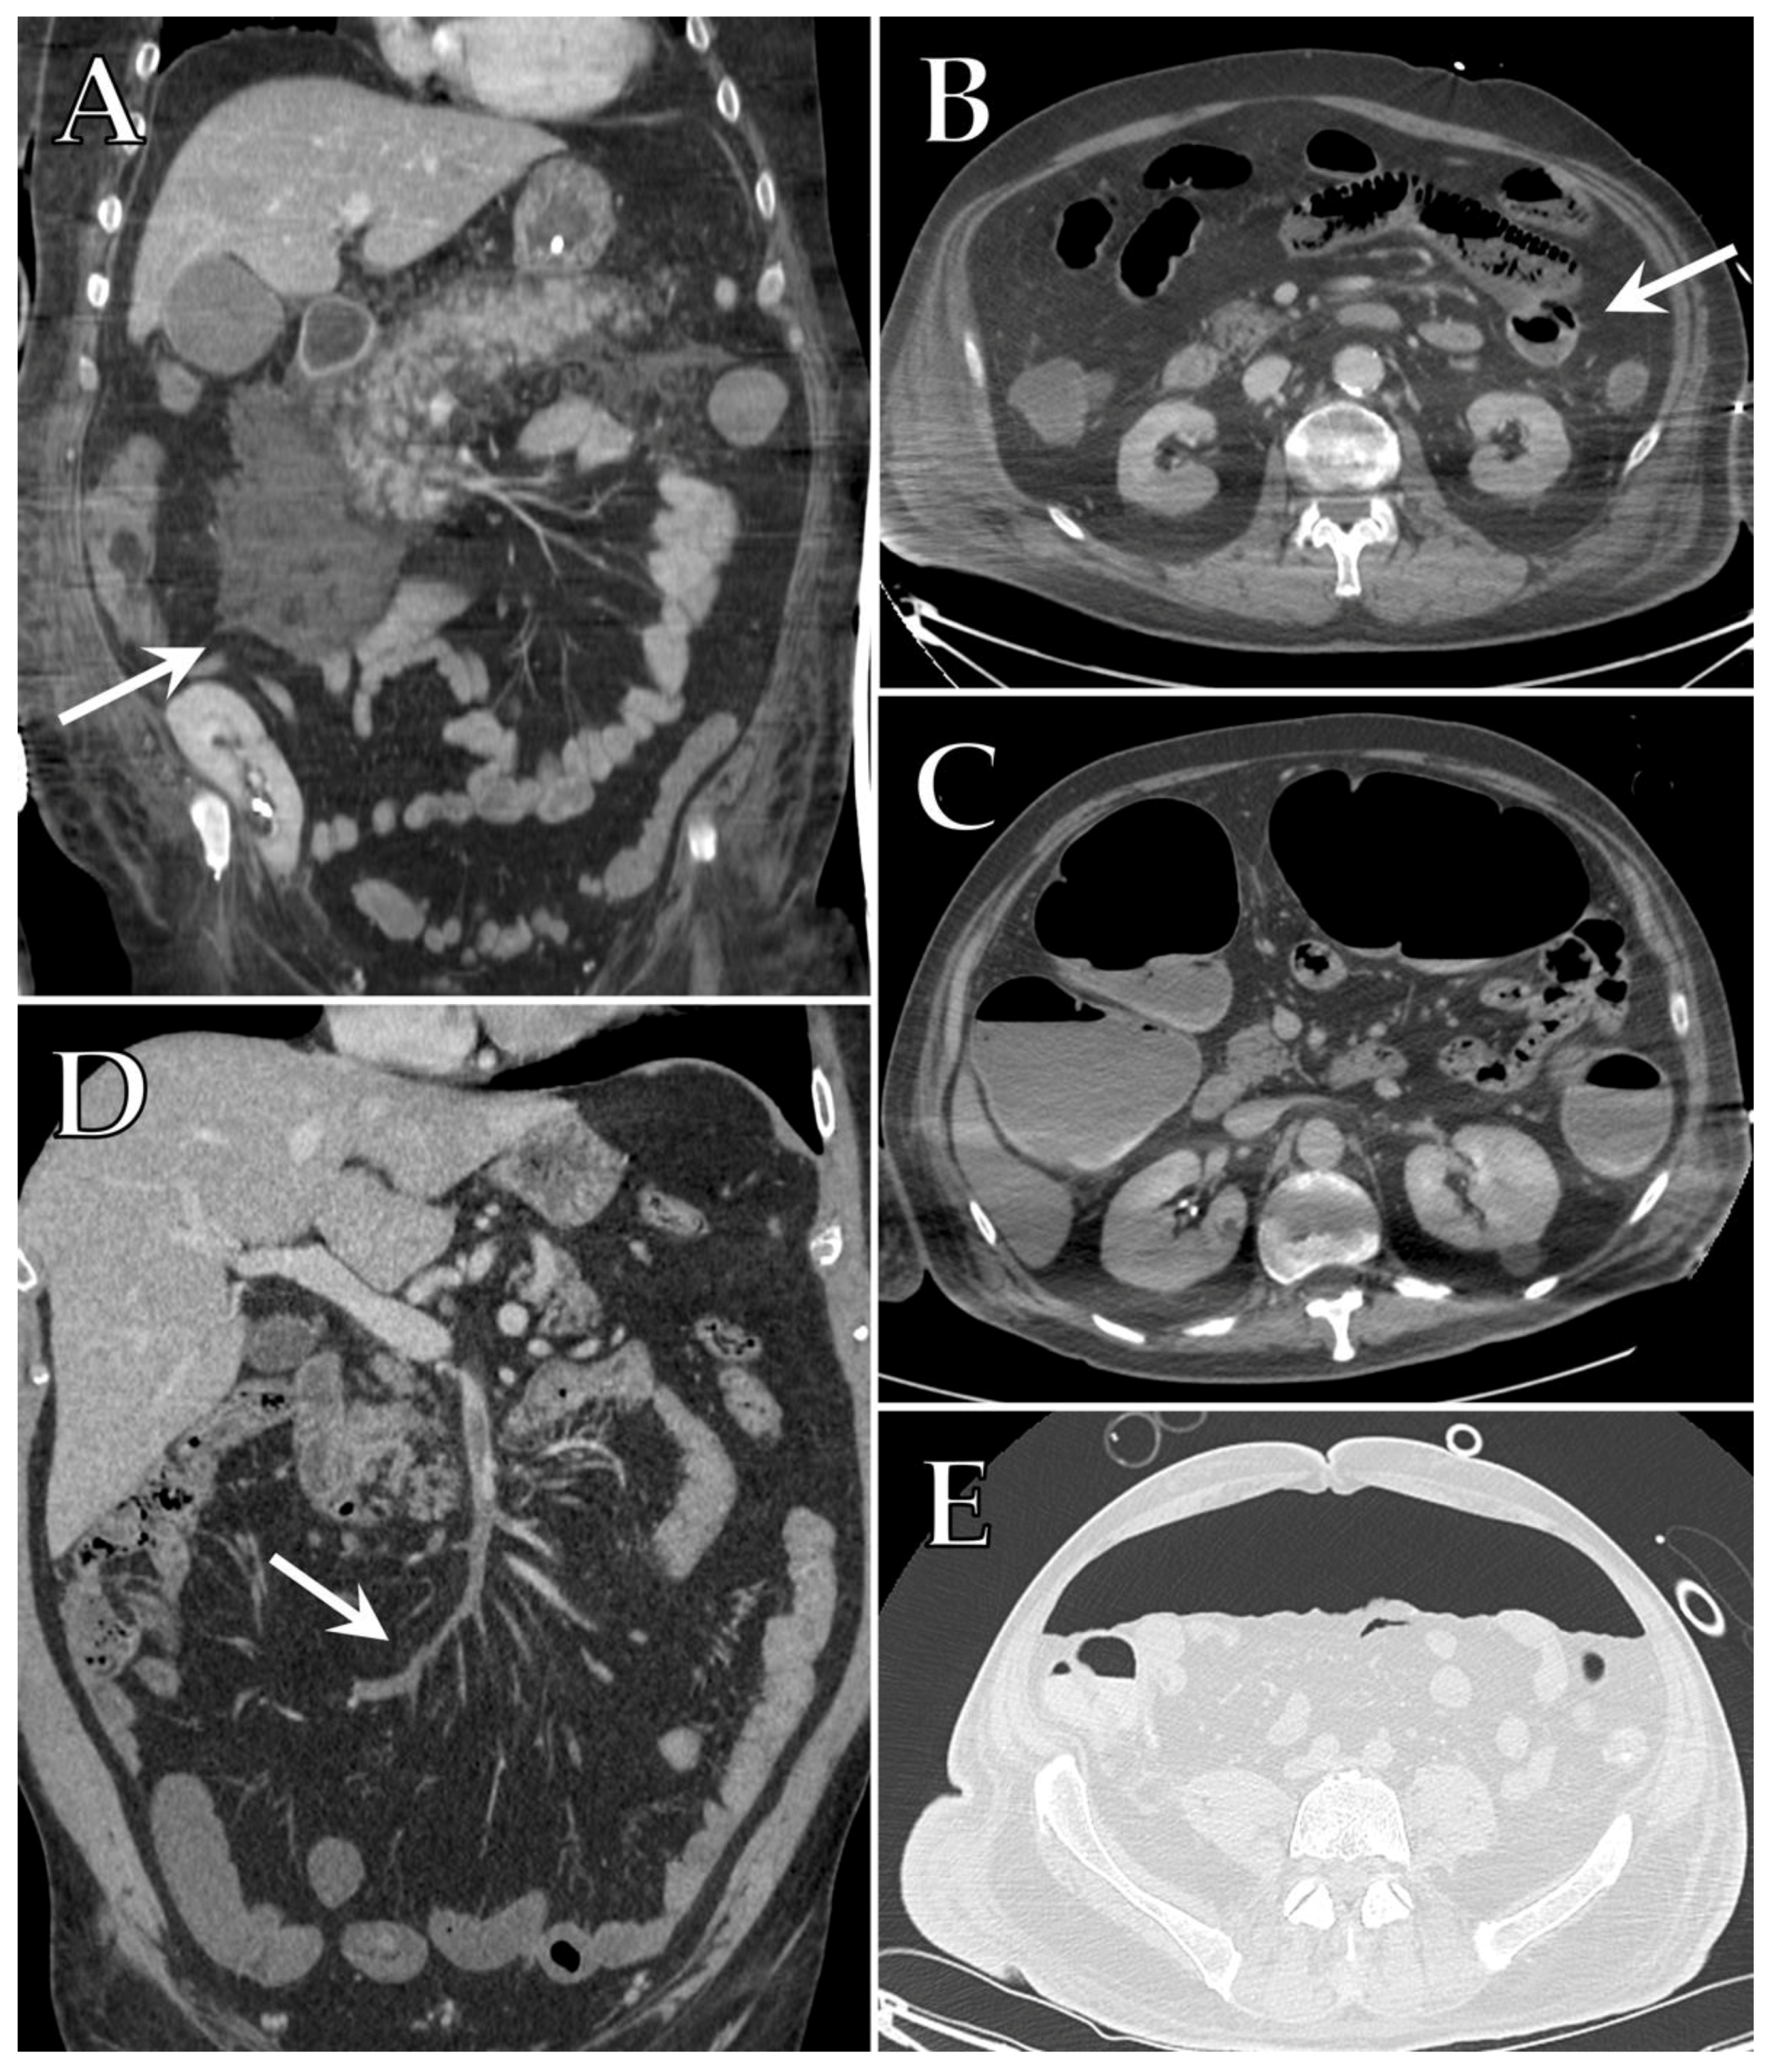

7. Gastrointestinal Complications

8. Renal Complications